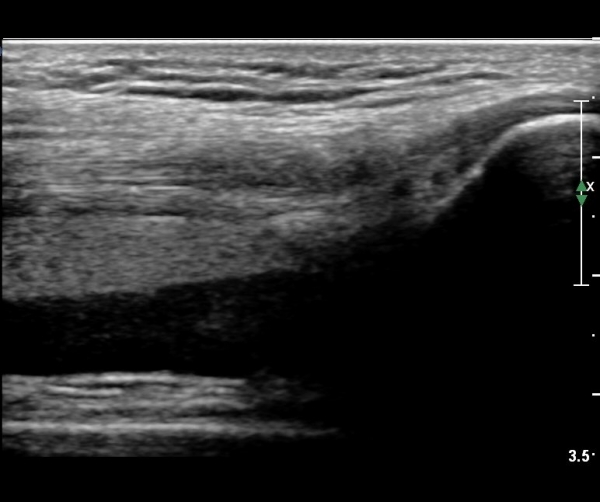

ÃÊÀ½ÆÄ °Ë»ç

¹«¸­ ÃøºÎ Á¾´Ü¸é°Ë»ç¿¡¼­ °í¿¡ÄÚ ¼ö¾×Àý·ù°¡ °üÂûµÊ( »çÁø 1).